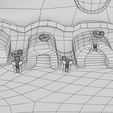

神经肌肉接头示意图